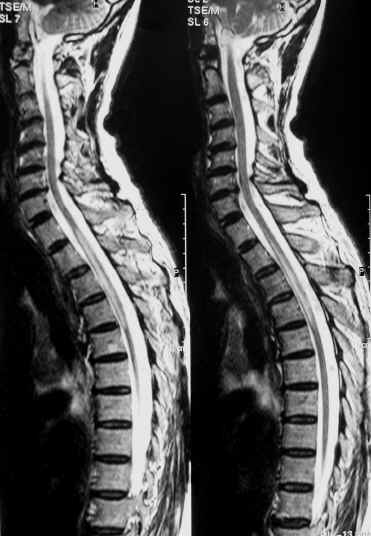

Transverse myelitis Pictures

The following images show the internal appearance of TM sufferers.

Picture of Transverse myelitis

Picture 1 – Transverse myelitis

Image of Transverse myelitis

Picture 2 – Transverse myelitis Image